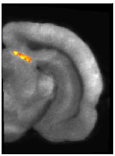

They enabled to accurately study stimulus-driven synaptic activity in vivo in a restricted rat brain region, the superior colliculus (Figure 1.2).

siRNA targeted against amyloid precursor protein impairs synaptic activity in vivo. A-S. Hérard, L. Besret, A. Dubois, J. Dauguet, T. Delzescaux, P. Hantraye, G. Bonvento and K.L. Moya. Neurobiology of Aging, 2006, 27(12):1740-50. Abstract.Figure 1.2. 3-D reconstruction of the left and right manually segmented superior colliculus. The automatic extraction of the "activated" volume using the threshold method is represented in red and the symmetric volume in green.